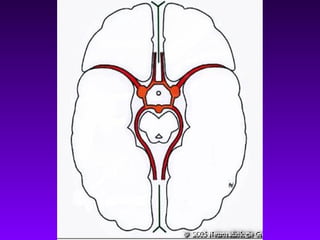

TDM cérébrale

En urgence reconnaîtla lésion hémorragique sous forme d’une zone spontanément hyperdense. La lésion ischémique est sans traduction (en phase initiale) ou se manifeste par une zone hypodense (après 24 h). TDM cérébrale